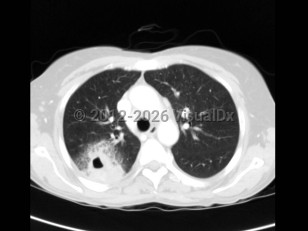

Imaging Studies image of Acinetobacter infection - imageId=6106611. Click to open in gallery.  caption: '<span>Acinetobacter community acquired pneumonia.</span>'

Acinetobacter community acquired pneumonia.